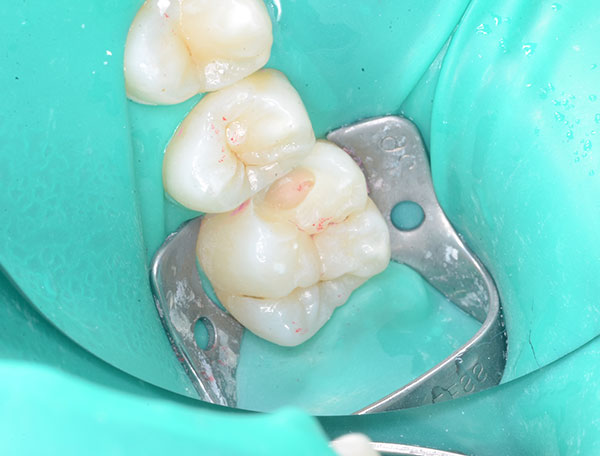

術前

術後

症例について

主訴:

最近冷たい物がよく染みる

治療内容:

炎症を起こした歯髄を部分的に除去し、神経をできるだけ残すことを目的とした治療です。

治療期間:90分 1回

費用:33,000円(税込)

治療に関わるリスクまたは副作用:

経過中に症状が出た場合、根管治療が必要になることがあります。